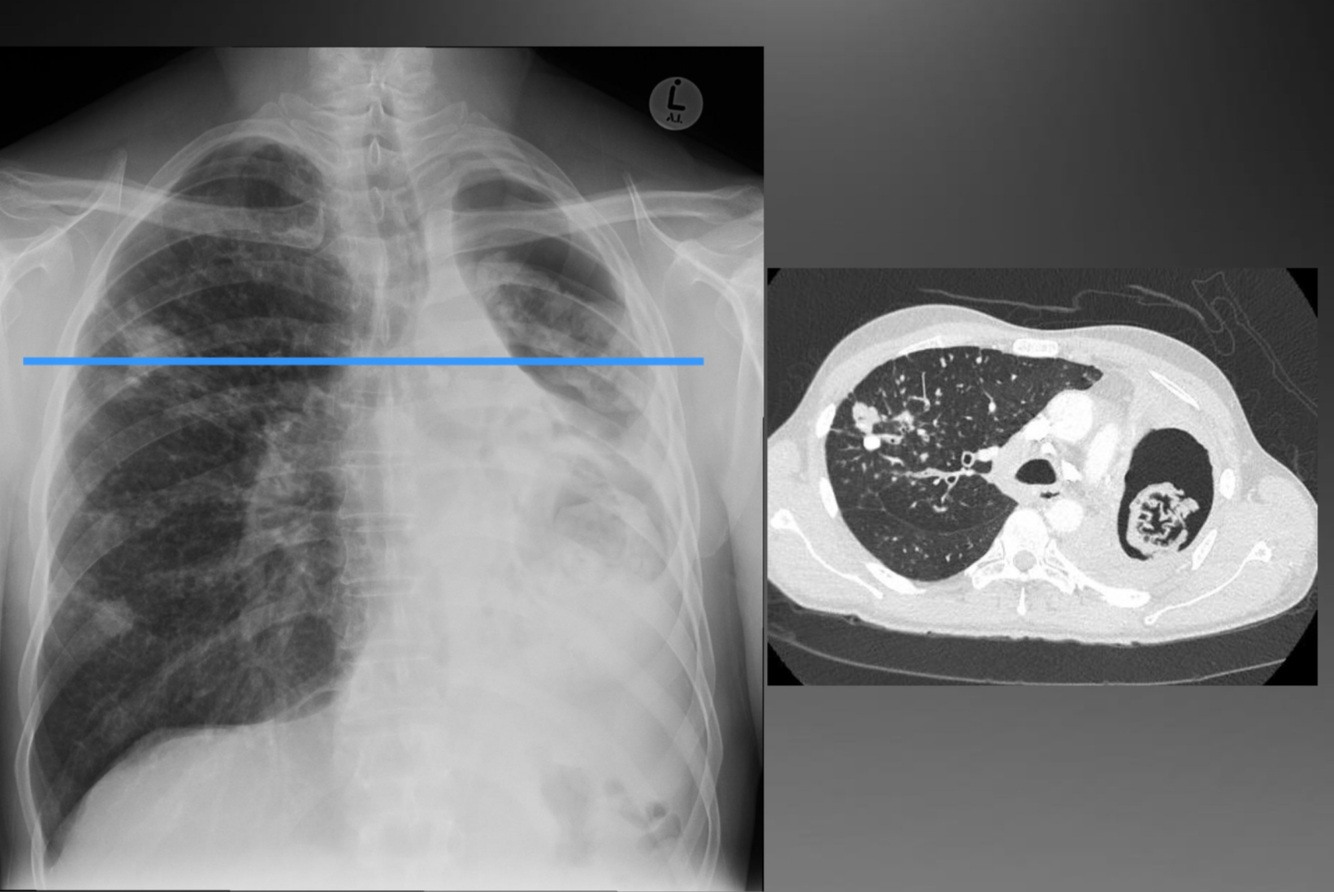

Consolidation and lymphadenopathy

Progressive primary tb

A

Less common

Rapidly progressive disease

CXR: extensive consolidation and

cavitation

Can mimic post primary MTB

infection

Progressive Primary Tuberculosis